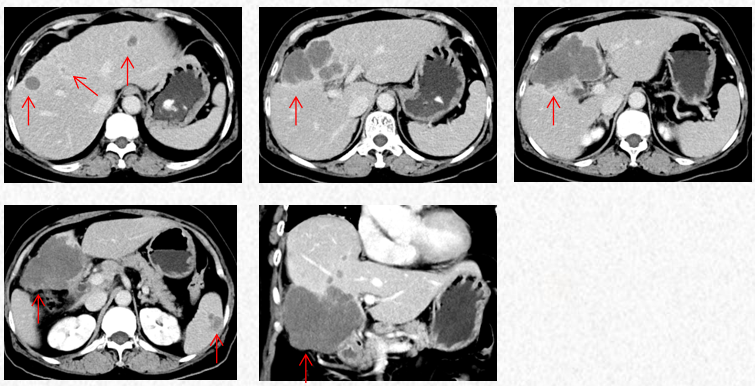

2022-11-30复查胸腹CT提示进展(PD)。

2022-11-30胸腹CT:肝肿物最大横截面积107*80mm(原病灶10*8cm),腹腔淋巴结最大10mm。新发脾脏转移瘤大小27*15mm。

2023-3-19胸腹CT:肝肿物最大横截面积91*60mm,脾脏转移瘤(19*12mm)

2023-5-22胸腹CT:肝肿物最大横截面积86*58mm,脾脏转移瘤(19*12mm)

2023-7-15胸腹CT:肝肿物最大横截面积86*58mm,脾脏转移瘤(19*12mm)